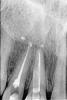

котик Опубликовано 11 мая, 2009 Автор Поделиться Опубликовано 11 мая, 2009 на снимке,кроме плохозалеченных зубов,не увидел ни одного импланта. Это снимок до имплантации переднего зуба, там где неправильно стоял штифт, мне его настоятельно рекомендовали удалить и поставить имплант, что я сделала, о чем теперь очень жалею. У меня вопрос а нужно ли было это делать Вот этот зуб вблизи, я ходила с ним пять лет и он меня не беспокоил кроме как того что десна немного наросла и иногда там карман образовывался. но это было редко. Может за пять лет раза три. Ну и конечно вид у него был сероватый , но терпимо, врачи сказали что лучше удалить и поставить имплант а то неизвестно что будет в будущем. Я так и сделала о чем теперь очень жалею. Ссылка на комментарий

котик Опубликовано 11 мая, 2009 Автор Поделиться Опубликовано 11 мая, 2009 извините, барышня....вы сюда пришли с какой целью - получить совет специалистов как решить вашу проблему? или рассказать,на примере некачественной работы, что все импланты - ***но? если первое,то разместите актуальные фотографии (желательно резкие и четкие) и снимки. также стоит описать диаметр имплантанта и его фирму-изготовителя, подробную хронологию событий. Если второе - не тратьте ваше и наше время. Это не форум "Cosmopoliten" и не комитет по защите стоматологических пациентов. Определитесь и действуйте. А то у меня сложное чувство относительно вас, что сейчас тема будет закрыта. PS. На прицельном снимке зуба - однозначное удаление. Штифт "протыкает" стенку корня. Если такой зуб оставить - проблем будет очень много. Так что не о чем жалеть. Извините может я погорячилась... просто до этого ходила со старым зубом, и горя не знала, а имплант вставила, что с десной не того и теперь не знаю как решить эту проблему... снимки имплантанта выложу сегодня вечером. Это снимок до имплантации переднего зуба, там где неправильно стоял штифт, мне его настоятельно рекомендовали удалить и поставить имплант, что я сделала, о чем теперь очень жалею. У меня вопрос а нужно ли было это делать Вот этот зуб вблизи, я ходила с ним пять лет и он меня не беспокоил кроме как того что десна немного наросла и иногда там карман образовывался. но это было редко. Может за пять лет раза три. Ну и конечно вид у него был сероватый , но терпимо, врачи сказали что лучше удалить и поставить имплант а то неизвестно что будет в будущем. Я так и сделала о чем теперь очень жалею. Но все равно интересно ведь я ходила же этим зубом пять и почему все было нормально? Ссылка на комментарий

котик Опубликовано 11 мая, 2009 Автор Поделиться Опубликовано 11 мая, 2009 Это снимок до имплантации переднего зуба, там где неправильно стоял штифт, мне его настоятельно рекомендовали удалить и поставить имплант, что я сделала, о чем теперь очень жалею. У меня вопрос а нужно ли было это делать Вот этот зуб вблизи, я ходила с ним пять лет и он меня не беспокоил кроме как того что десна немного наросла и иногда там карман образовывался. но это было редко. Может за пять лет раза три. Ну и конечно вид у него был сероватый , но терпимо, врачи сказали что лучше удалить и поставить имплант а то неизвестно что будет в будущем. Я так и сделала о чем теперь очень жалею. Сейчас пришла от француского стоматолога, он сказал что непонятно почему удалили зуб если ничего не беспокоило...и сказал что можно было поставить коронку, и у меня возникает вопрос почему ни один из трех врачей мне не предложил этого сделать? Вернее когда я заикнулась у третьего врача, н сказал что я рискую? А в чем риск то был? Непонятно мне совсем, объясните. Конечно после драки кулаками не машут. но все-таки....Сказал что ничего уже нельзя исправить. что в любом случае после удаления идет усадка кости о чем меня должны были предупредить, но конечно же никто и не заикнулся об этом. Вариант оставить все как есть. Снимки импланта выложу завтра. Ссылка на комментарий

котик Опубликовано 11 мая, 2009 Автор Поделиться Опубликовано 11 мая, 2009 французский стоматолог отжог.во-первых, коронку на этот зуб ставить нельзя.Там перфорация корня. Начнет кость "гнить".во-вторых, все можно исправить и фото подтверждение у вас есть. Передайте жителю парижа - учи матчасть! Вы бы видели какой мне шуруп ввинтили, завтра выложу, просто они мне забыли снимок на флешку сбросить, там малой кровью не обойдешься, если удалять что с челюстью, во первых надо денег до фига на все это, во вторых железную психику чего у меня нет, я на это то не знаю как решилась А что такое перфорация? И еще разве удаляют зубы, когда ничего не беспокоить, а такой вариант не лучше, вот когда проблемы начнуться вот тогда и будем их решать. Ссылка на комментарий